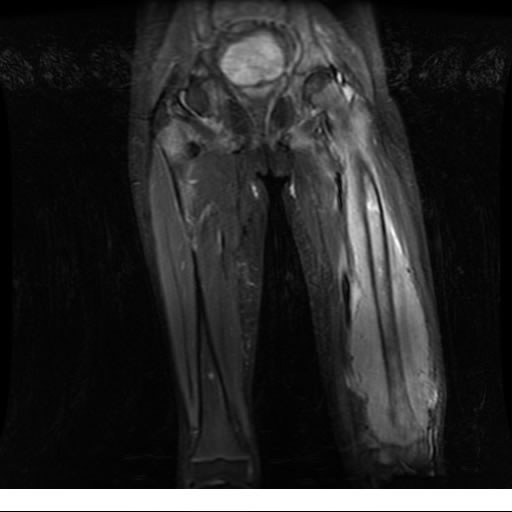

Se realiza estudio de MRI de muslo izquierdo en diferentes planos, con secuencias de Spin Echo, GRE; ponderadas a T1 y a T2, se utilizan pulsos de saturación de grasa y se administra medio de contraste IV a base de Gadolinio en base al peso del paciente.

La diáfisis femoral izquierda muestra reacción perióstica importante, se extiende desde el cuello del fémur, invade trocánteres, diáfisis femoral, medial y distal, es compatible con un proceso infeccioso óseo, el complejo muscular del muslo se ve edematizado.

Hallazgos en Resonancia Magnética (RM)

La resonancia es la modalidad de elección para valorar la extensión intramedular y la infiltración en tejidos blandos, brindando una imagen más detallada del compromiso tumoral. Los hallazgos característicos incluyen:

Lesión de señal heterogénea en secuencias T1 (hipointensa) y T2/STIR (hiperintensa), que refleja necrosis, hemorragia y contenido celular diverso.

Realce intenso y heterogéneo tras la administración de contraste (gadolino), lo que indica vascularización tumoral.

Compromiso de la médula ósea adyacente y de estructuras vecinas, como músculos y neurovasculatura.

Posible presencia de edema óseo y necrosis central.